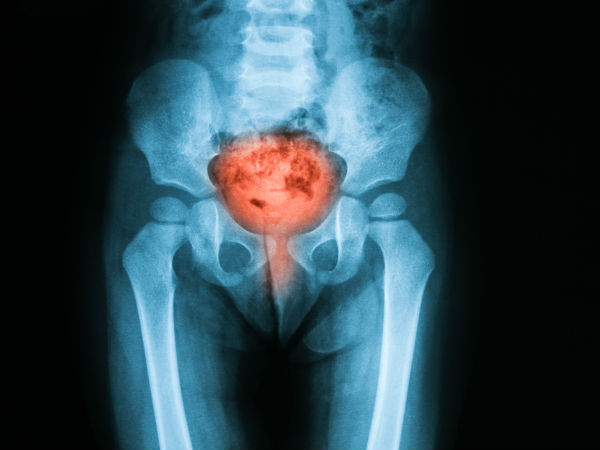

3. पेल्विक इन्फेक्शन

यह इन्फेक्शन बहुत दुर्लभ है, लेकिन जब ऐसा होता है तो आपको दवाएं नस में दी जाती हैं। अंडाशय, गर्भाशय और फैलोपियन को ऑपरेशन से निकाल दिया जाता है।